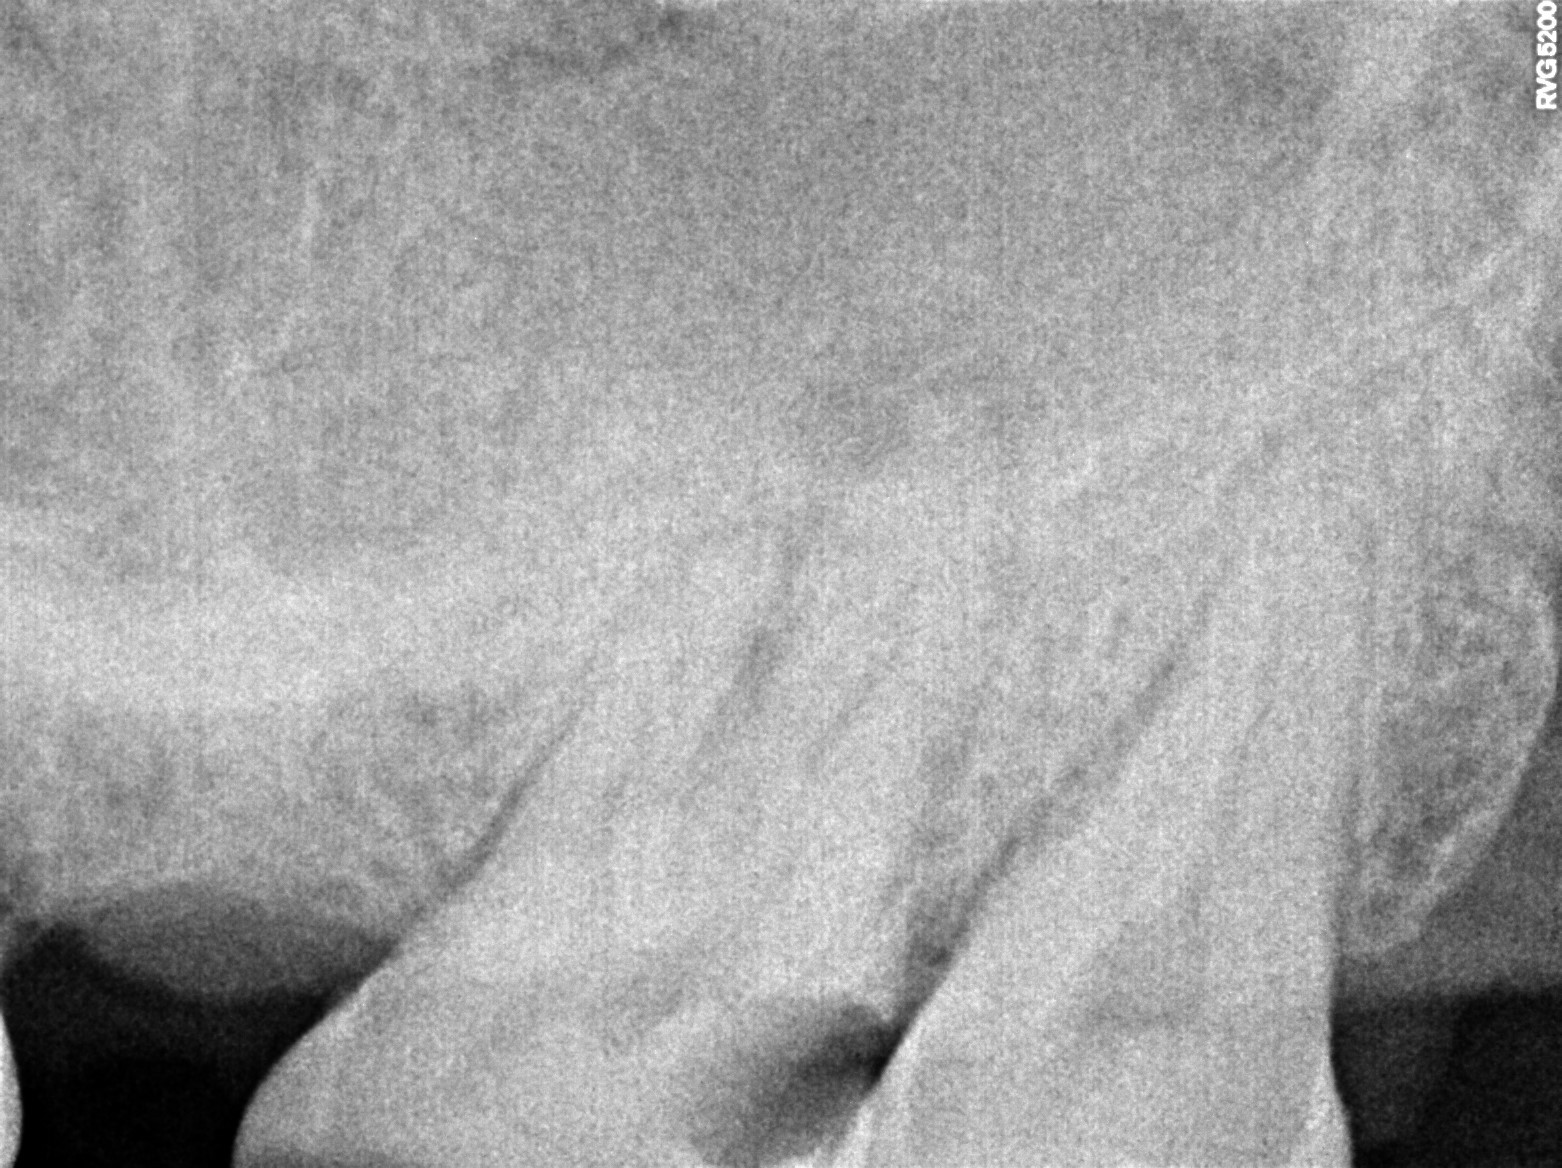

Dental Radiographs FHIR: DocumentReference · LOINC 24641-7

xray_1773075490_1.jpg

24641-7